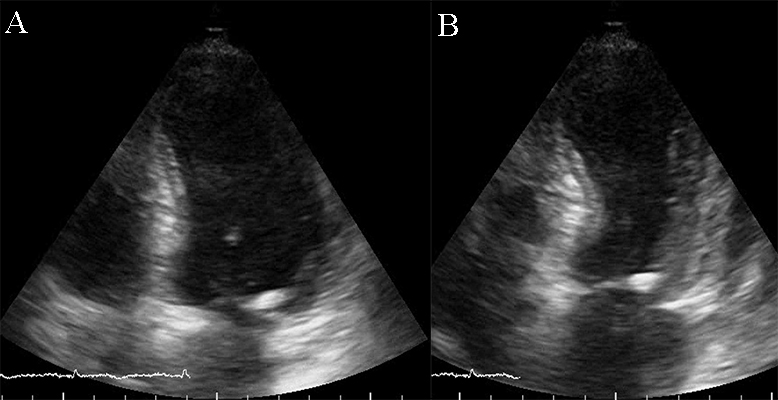

Restrictive cardiomyopathy (RCM) is characterized by non-dilated ventricles, mild or no myocardial hypertrophy with impaired ventricular filling, thus it is defined by abnormal ventricular diastolic function with a normal size LV (see Fig. 8). In the early stages of the disease, the systolic function of the LV is also normal [38].

Fig. 8.The echocardiographic aspect of RCM in an elderly patient presenting with signs and symptoms of heart failure. Apical 4 chamber view showing severe biatrial enlargement, with left atrial thrombus and non-dilated left and right ventricles.

The causes of RCM can be classified as non-infiltrative (familial) or infiltrative (storage diseases), but the same pattern can be found in other disorders like diabetic cardiomyopathy, scleroderma, and endomyocardial fibrosis [38, 39, 40]. An accurate myocardial investigation by MRI and myocardial scintigraphy allows the diagnosis of different types of myocardial amyloidosis which is increasingly observed in the elderly either by transthyretin (aTTR) or by AL–light immunoglobulin chains in different plasmacytomas [41]. Another type of RCM is found in sarcoidosis and it can cause global or regional LV wall motion abnormalities. In some cases, the changes are specifically revealed on the basal posterior and lateral wall of the LV [42, 43, 44]. The most common finding is myocardial thinning, but RCM can also present with hypertrophy or it can include myocardial aneurysms [38, 45, 46, 47]. In some RCMs such as endomyocardial fibrosis or hypereosinophilic syndrome apical intraventricular thrombosis may be recognized; this may be responsible for pulmonary or systemic cardioembolism [48]. In RCM due to amyloidosis, apart from hypertrophy and wall motion abnormalities (Fig. 9), valvular involvement may also be noted with thickened aortic cusps or mitral leaflets determined by local deposition of amyloid [49].

Fig. 9.The echocardiographic aspect of cardiac amyloidosis, associated with aortic stenosis. (A) short-axis view, showing left ventricular hypertrophy. (B) Speckle tracking echocardiography obtained by measuring longitudinal strain in apical 4 chamber view, shows a significantly reduced GLS (global longitudinal strain) of –8.6%.

2D echocardiography, as mentioned before, highlights a low or normal diastolic volume of the LV associated with normal or only mildly reduced LV ejection fraction, as criteria for RCM. Also, one or both atrial enlargement is identified, with increased pressures, and normal pericardium. Once the typical pattern of RCM is identified, the echocardiogram can reveal also some features for a specific etiology. For example, in cardiac amyloidosis, the left and right ventricular walls are often mildly and symmetrically thickened, the myocardium may have a granular appearance, and myocardial strain imaging may show preserved apical function. However, it is not sufficient information neither to confirm, nor exclude cardiac amyloidosis [39, 40, 50], and further testing is needed. Moreover, in sarcoidosis global or regional (typically basal posterior and lateral) LV wall motion abnormalities may be observed. The most common finding is myocardial thinning, while less common findings include myocardial aneurysms, hypertrophy, and pericardial effusion [51, 52]. In eosinophilic inflammation of the myocardium or hypereosinophilic syndrome, the echocardiogram is often unrevealing during the initial necrotic stage. In the thrombotic stage of the disease, the damaged endocardium may have associated thrombus, predominantly involving the ventricular apex [3, 5, 38, 52, 53]. During the last, fibrotic stage, increased endomyocardial echogenicity is seen, affecting one or both ventricles, sometimes with overlying thrombus; the ventricular filling can be restricted, and atrioventricular valve leaflets may be tethered [53, 54, 55]. A pattern similar to hypereosinophilic syndrome can emerge in endomyocardial fibrosis. It may be characterized by LV, RV, or biventricular apical fibrosis [53, 54, 55]. In radiation-induced RCM the echocardiogram may show structural abnormalities within the field of radiation, such as calcified heart valves, a thickened pericardium, or focal wall motion abnormalities related or not to radiation-associated coronary artery disease [40, 42, 56, 57].